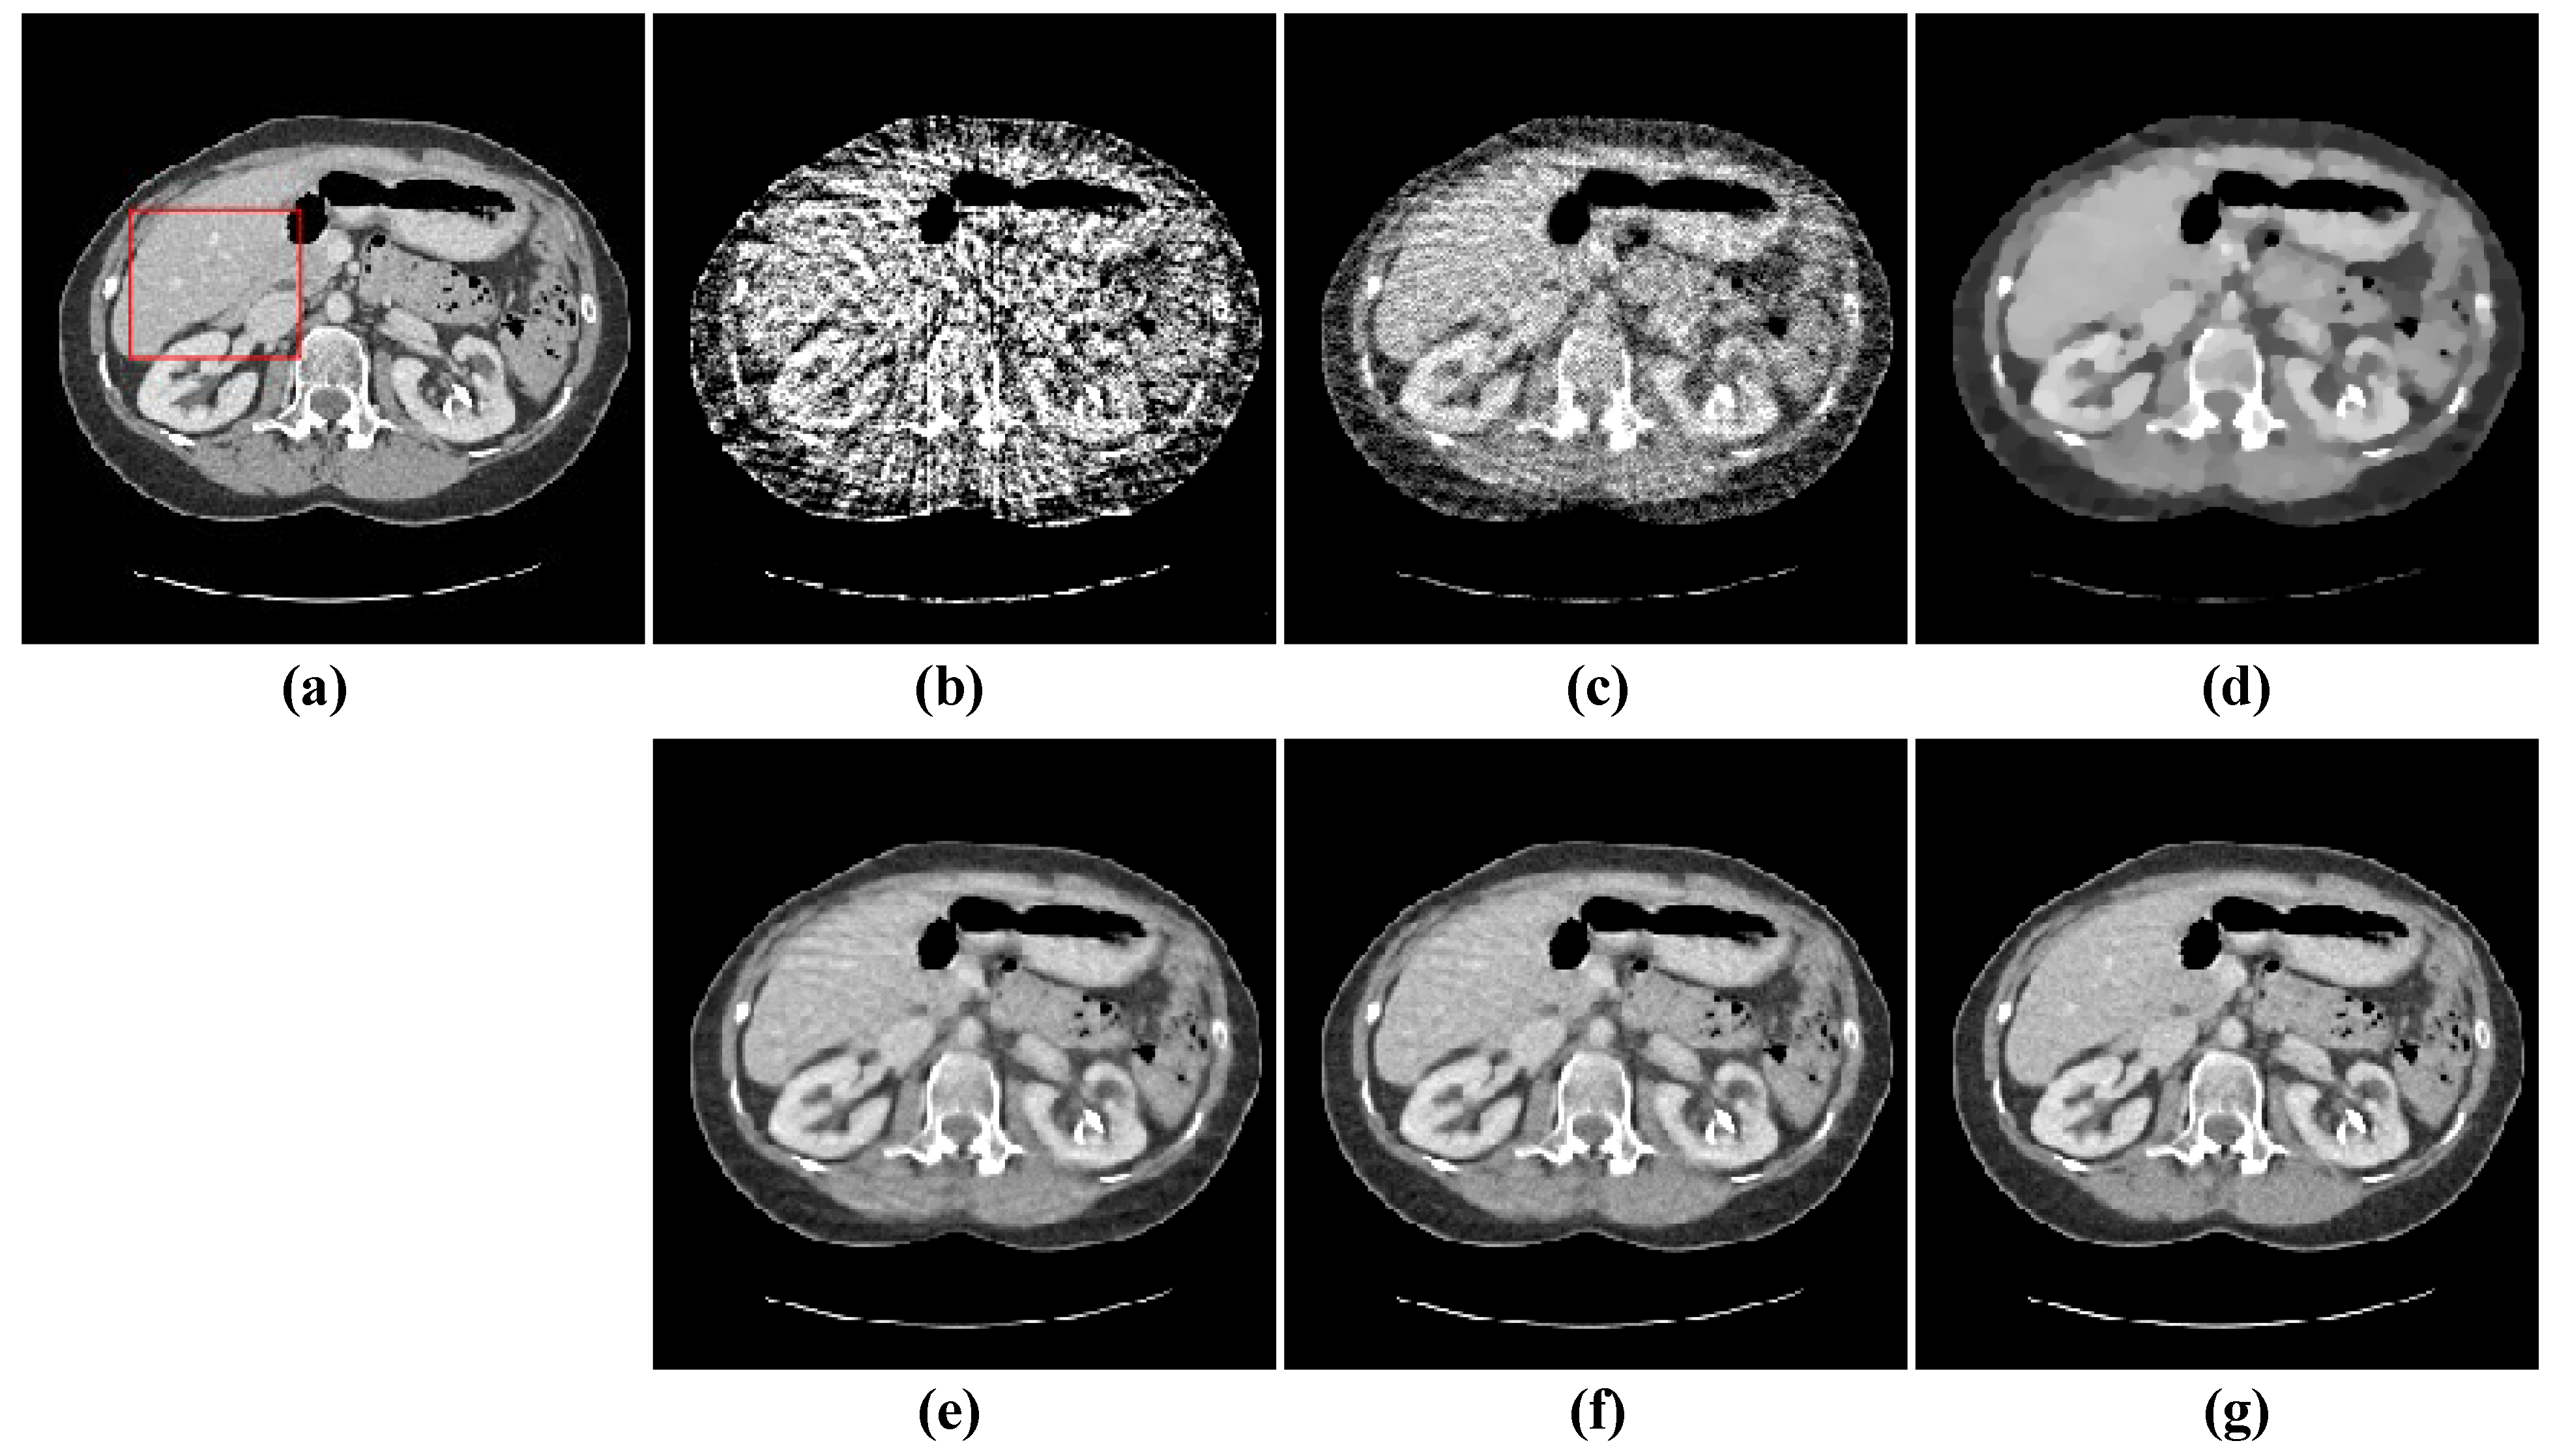

The first image reconstruction experiment is using a pelvic image to show the feasibility of our algorithm for SVCT reconstruction, as shown in Figure 1. We extracted 80, 64, and 48 views from a full scan and selected parameters empirically. The parameters are set as follows: a = 0.5, γ1 = 0.3, and γ2 = 0.08. Figure 2, Figure 3 and Figure 4 show the ground truth and reconstruction images via FBP, OS-SART, TV, PICCS, TVPI-G, and our method NPICCS. From these figures, it is evident that our algorithm outperforms the other methods in terms of recovering image structures and suppressing noise. Specifically, the FBP and OS-SART results (as shown in Figure 2b,c, Figure 3b,c and Figure 4b,c) contain high levels of noise and artifacts, while TV results (as shown in Figure 2d, Figure 3d and Figure 4d) are characterized by blurring and staircasing effects. The PICCS and TVPI-G methods provide better results than the other approaches because of the introduction of prior information, but image edges are missing as shown in Figure 2e,f, Figure 3e,f and Figure 4e,f. At the same time, it can be seen that our method is able to preserve image edges and suppress noise effectively, as shown in Figure 2g, Figure 3g and Figure 4g.

Figure 3. 64 views reconstruction results of pelvic image: (a) ground truth, (b) FBP, (c) OS-SART, (d) TV, (e) PICCS, (f) TVPI-G, and (g) NPICCS. The display window is [−150 250] HU.

Applsci 13 10320 g003

Figure 4. 80 views reconstruction results of pelvic image: (a) ground truth, (b) FBP, (c) OS-SART, (d) TV, (e) PICCS, (f) TVPI-G, and (g) NPICCS. The display window is [−150 250] HU.

Applsci 13 10320 g004